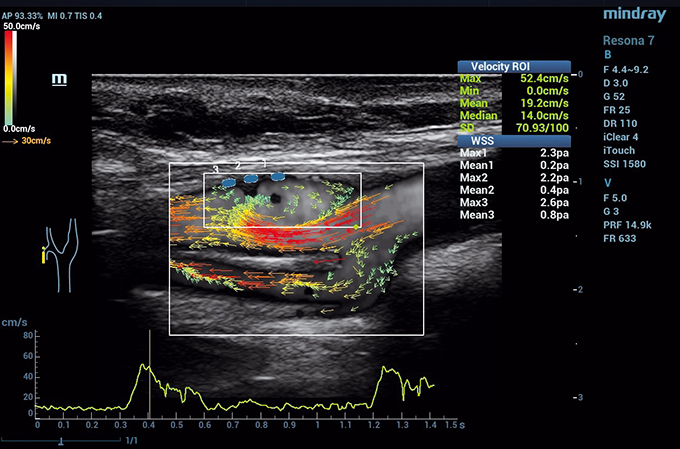

A parlare è Alfredo Goddi, Medico specializzato in radiodiagnostica, a capo del Centro Medico SME Diagnostica per Immagini di Varese, in prima linea in quella che viene definita medicina predittiva. Ovvero quella branca della medicina in grado di prevedere il manifestarsi di alcune specifiche patologie, in soggetti potenzialmente a rischio, che tuttavia non ne sono ancora affetti. “L’applicazione più recente che ci sta facendo lavorare parecchio in quest’ambito è quella relativa ad una nuova tecnologia chiamata Vector Flow Imaging, un sistema che analizza i vettori di flusso che stanno dietro al movimento dei globuli rossi – racconta ancora Goddi –. Per dirla in un altro modo, ci stiamo interessando di fluidodinamica del sangue all’interno dei vasi, applicando questa tecnica molto sofisticata ad altissima risoluzione (200 micron, ovvero 2 decimi di millimetro) tale da vedere come si muovono nel tempo i globuli rossi all’interno dei vasi”. Si tratta di una tecnologia sviluppata da un’azienda danese e da una cinese che, al momento, viene utilizzata per lo studio delle carotidi e permette di avere delle informazioni che prima erano impossibili da conoscere. Grazie soprattutto ad una sorta di analisi “alla moviola” di quello che accade nelle arterie: “In un secondo e mezzo si arrivano a generare da 600 fino a 1.400 immagini, il che ci dà la possibilità di scattare una fotografia altamente dettagliata del flusso dei globuli rossi: un presupposto fondamentale per capire quali pazienti sono a rischio di sviluppare, ad esempio, delle placche arteriosclerotiche. Proprio a causa di uno specifico movimento dei globuli rossi, tipico di un paziente e non di un altro, perché dipende dalla geometria e dalla conformazione genetica che hanno i vasi stessi”, specifica il dottor Goddi.

Il Centro SME, insieme al Dipartimento di Fisica Medica dell’Università dell’Insubria di Varese, al Dipartimento di Diagnostica dell’Università di Pavia e al Dipartimento di Management, Information and Production Engineering dell’Università di Bergamo, ha realizzato la parte di validazione clinica di questa tecnologia, aprendo così le porte ad una medicina di tipo predittivo: “L’obiettivo è studiare oggi un 25enne con una situazione anatomica sfavorevole, che potrebbe portarlo a sviluppare determinate patologie in futuro e non curare il paziente di 50-60 anni che quelle disfunzioni le ha già – precisa Alfredo Goddi – .Modificando lo stile di vita in età giovanile, si eviterà di ritrovarsi con tutti i problemi che oggi siamo costretti a trattare nell’adulto e nell’anziano. Si diminuirà, per esempio, il rischio di incidenti cardiovascolari, non dimenticando che sono la prima causa di morte”.